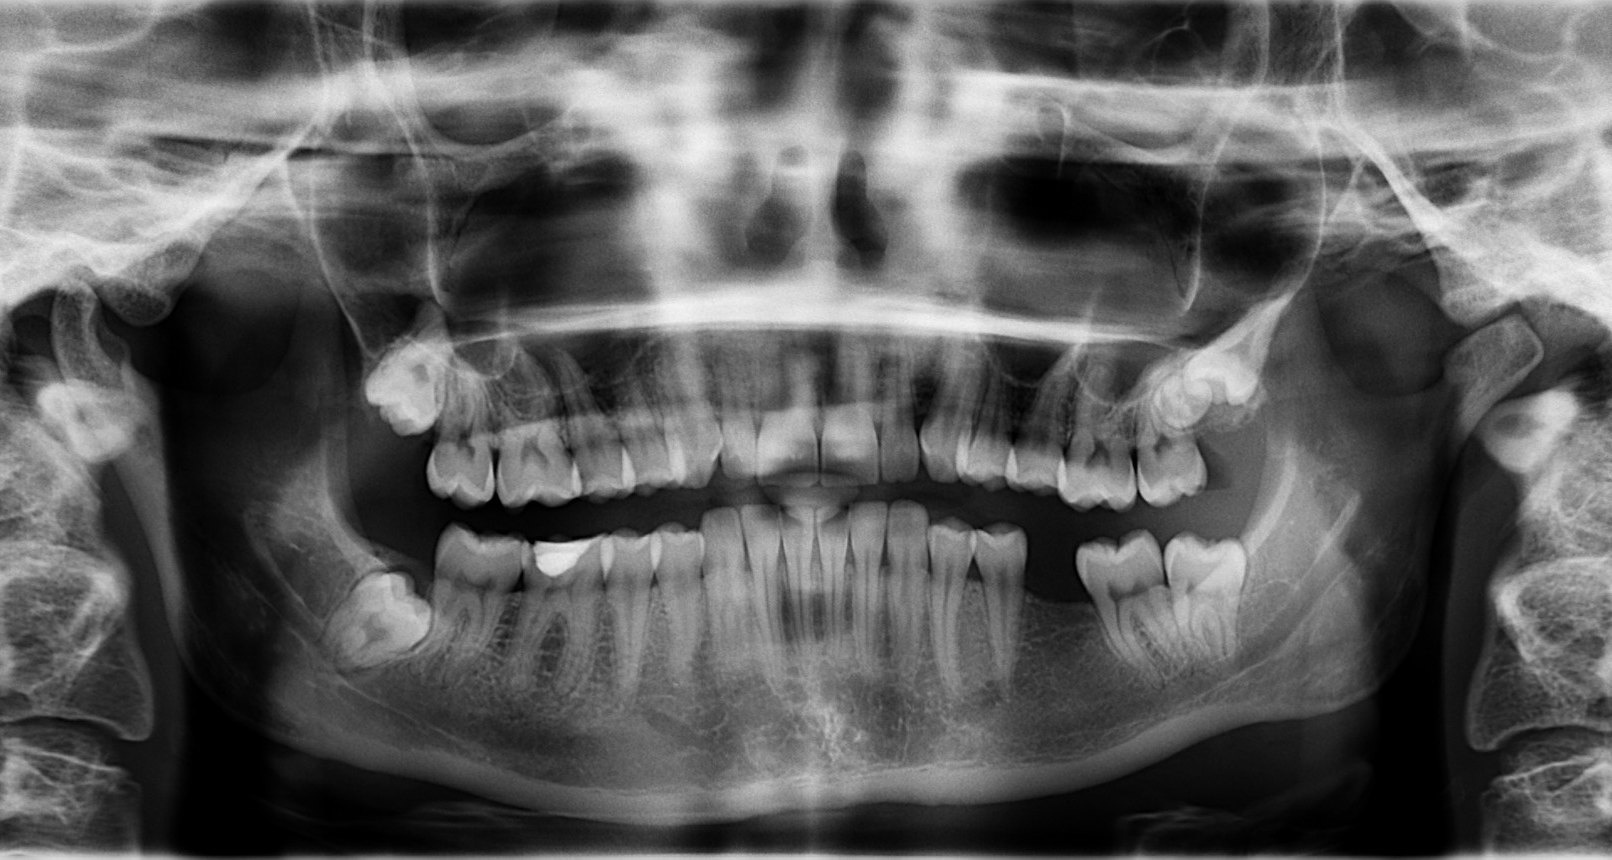

Для костей прочность - важнейшая характеристика, ведь среди основных механических функций всего скелета опора, движение и защита внутренних органов. Если удалить полностью весь скелет из нашего тела мы не только похудеем в среднем на 15%. Представьте себе здоровенный мешок с киселем - именно так будет выглядеть человек без скелета. Мы даже не сможем сдвинуться с места.